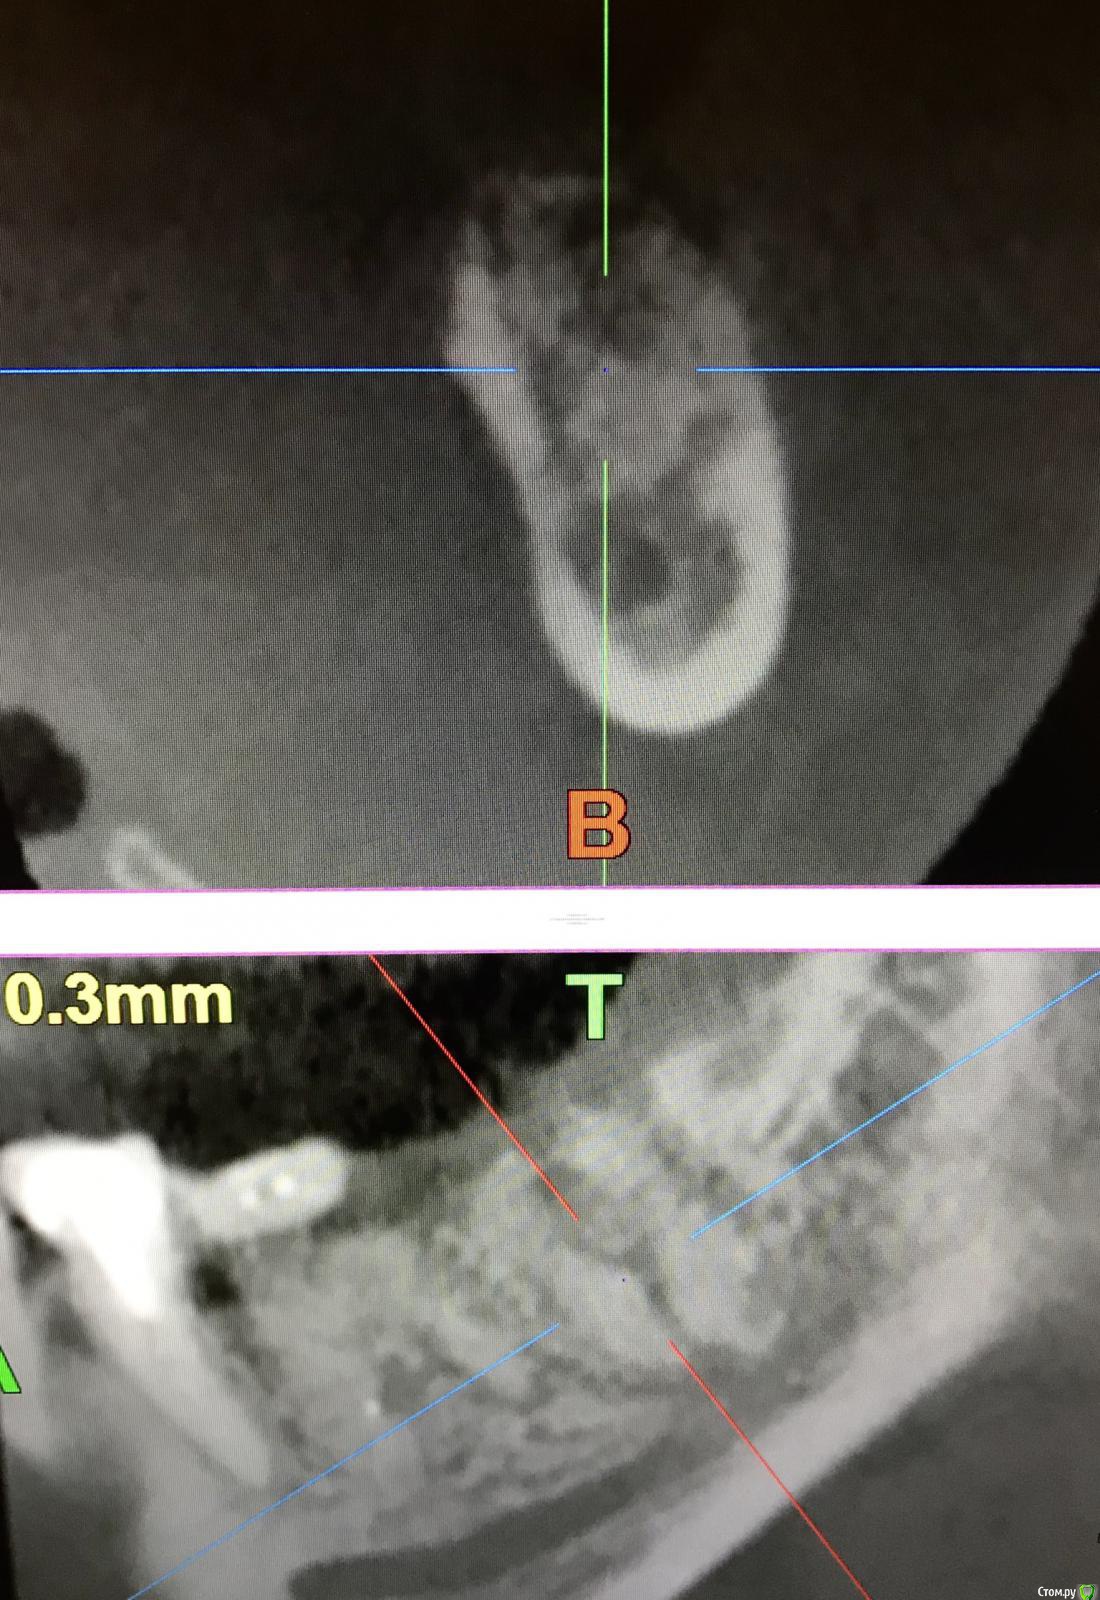

annda Опубликовано 7 августа, 2018 Поделиться Опубликовано 7 августа, 2018 (изменено) Тоже попробовала.Застарелый перелом корня.Два свища на момент приема.Удаление всего,спилила на коронковом фрагменте до связки,канал закрыла IRMом,в дефект порошок Лилпласт на АPRF ,обратно фрагмент притопила,фиксация на ретейнер.Снимок через две недели.Теперь думаю,не длинноват ли фрагмент.Хотя,может и проекция снимка вводит в заблуждение.КТ срезы сняла с экрана,пардон за качество. Изменено 7 августа, 2018 пользователем annda 3 Ссылка на комментарий

Bier Опубликовано 7 августа, 2018 Автор Поделиться Опубликовано 7 августа, 2018 ну вроде как длинный фрагмент даже лучше. Советую через 2-3 мес вытянуть его ортодонтически и только потом удалить. Ссылка на комментарий

annda Опубликовано 8 августа, 2018 Поделиться Опубликовано 8 августа, 2018 (изменено) Ортодонтически—может просто ретейнер переклеить?Он не обожжен... Изменено 8 августа, 2018 пользователем annda Ссылка на комментарий